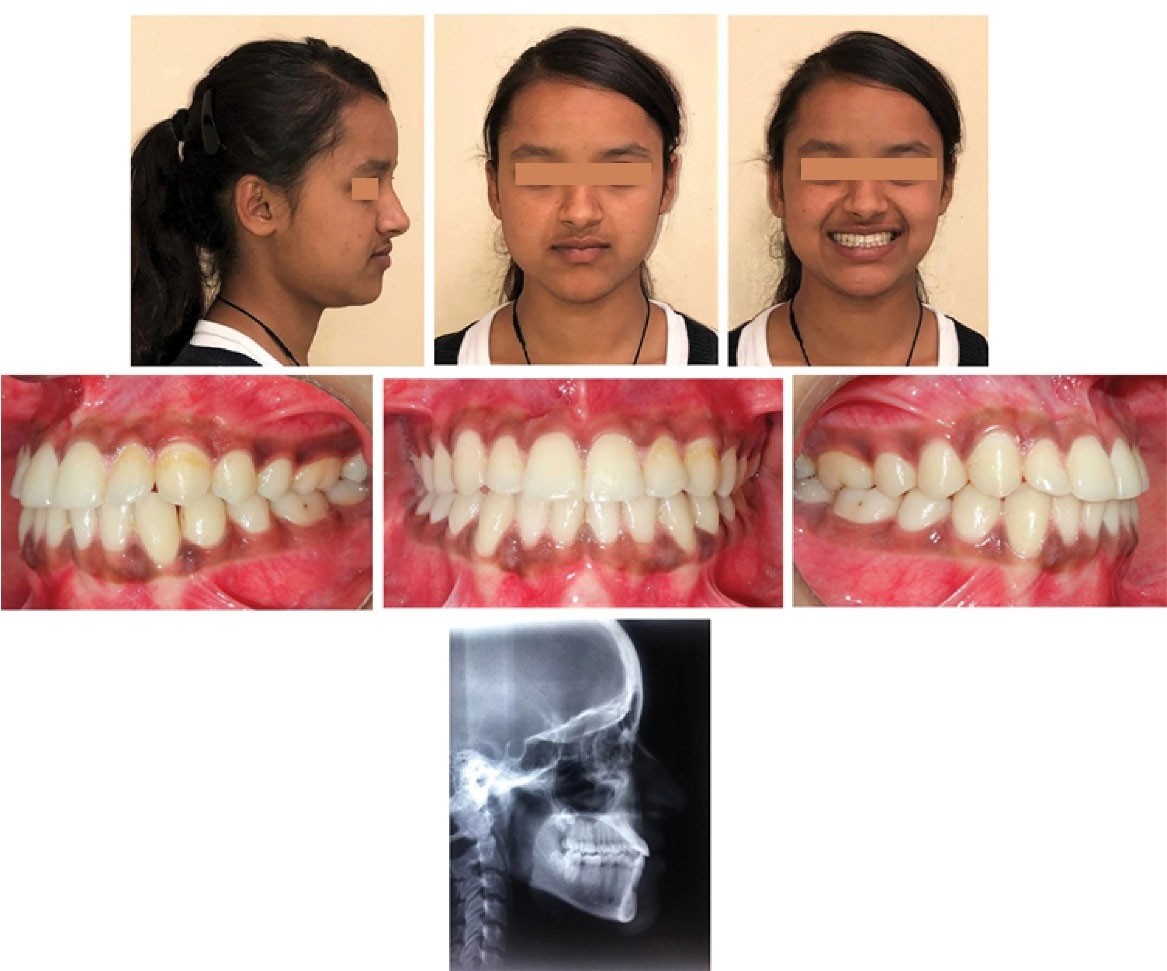

At 2.5-year and 4-year follow-up appointments, the harmonious facial balance and intermaxillary dental relationships were well-maintained ( and ).

Figure 8.

2.5-year follow-up demonstrating the stability of achieved results.

Figure 9.

Clinically and radiographically stable results at 4-year follow-up.